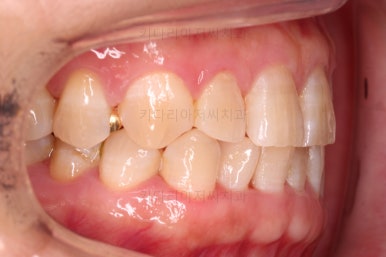

부산교정치료 전후사진을 비교해 보겠습니다.

쓰러진 치아도 원위치로 만들어 기능을 회복시켜주었고, 임플란트도 1개로 마무리를 할 수 있었어요.

이렇게 단순히 임플란트를 해야 하는 상황도 간단한 교정치료와 병행한다면 치아도 아끼고 임플란트도 줄이는 매우 좋은 치료가 될 수 있답니다.